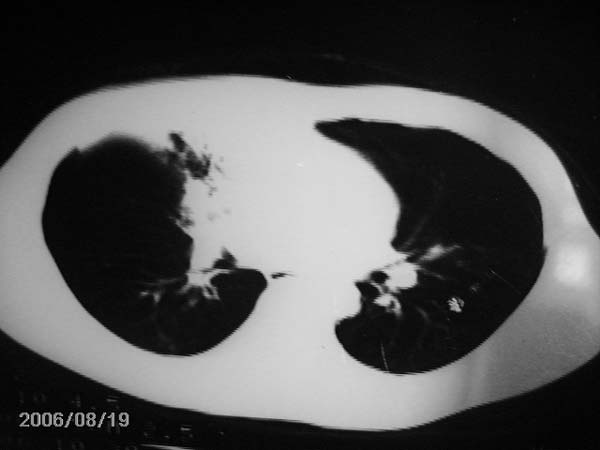

男,13岁,发烧半月,干咳无痰,正规使用抗生素半月,现在仍是午后低烧!!!未做痰检

右中肺呈大片状密度欠均匀影,内见含气支气管.

结合病史,考虑:右中肺大叶性肺炎(吸收期).

右肺中叶大片状密度增高影,内密度不均匀,右肺门处增大,应该是淋巴结肿大,结合临床首先考虑原发性肺结合可能性大,不排除合并感染可能,建议治疗后复查.

右肺结核,干酪性肺炎形成

灶内密度不均,似乎有囊状,条状影,考虑右中叶综合症; 从照片中看不出有无钙化灶,若明显则考虑结核性。

考虑中叶综合征(右肺门肿大淋巴结伴中叶阻塞性炎症)